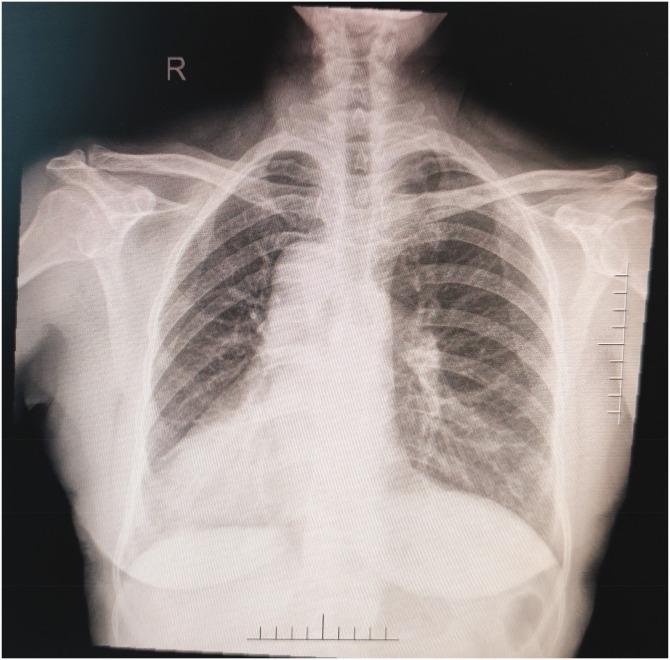

Dextrocardia is a congenital abnormal position of the heart in which the main part of the heart is in the right chest, and the long axis of the heart points to the lower right. Cases of a combination of dextrocardia and sick sinus syndrome are rare. A 65-year-old female patient was admitted to hospital with palpitations and dizziness for 1 week. Mirror-image dextrocardia and sick sinus syndrome were diagnosed by an electrocardiogram, echocardiography, Holter monitoring, and X-rays. Finally, we successfully implanted a dual-chamber pacemaker into the patient. The patient had an uneventful recovery and was discharged when her symptoms had greatly improved 1 week later. When dextrocardia is present, using active fixation leads in the atrial and ventricular leads is easier for finding the pacing position with optimal sensing and pacing thresholds, and they reduce the incidence of falling off.

右位心是一种先天性的心脏位置异常,主要部分位于右侧胸部,心脏的长轴指向右下。右位心合并病态窦房结综合征的病例较为罕见。一位 65 岁女性患者因心悸和头晕 1 周入院。心电图、超声心动图、动态心电图监测和 X 线检查诊断为镜像右位心和病态窦房结综合征。最终,我们成功地为患者植入了双腔起搏器。患者恢复顺利,1 周后症状明显改善时出院。当存在右位心时,使用主动固定的心房和心室导线更容易找到具有最佳感知和起搏阈值的起搏位置,并降低脱位的发生率。